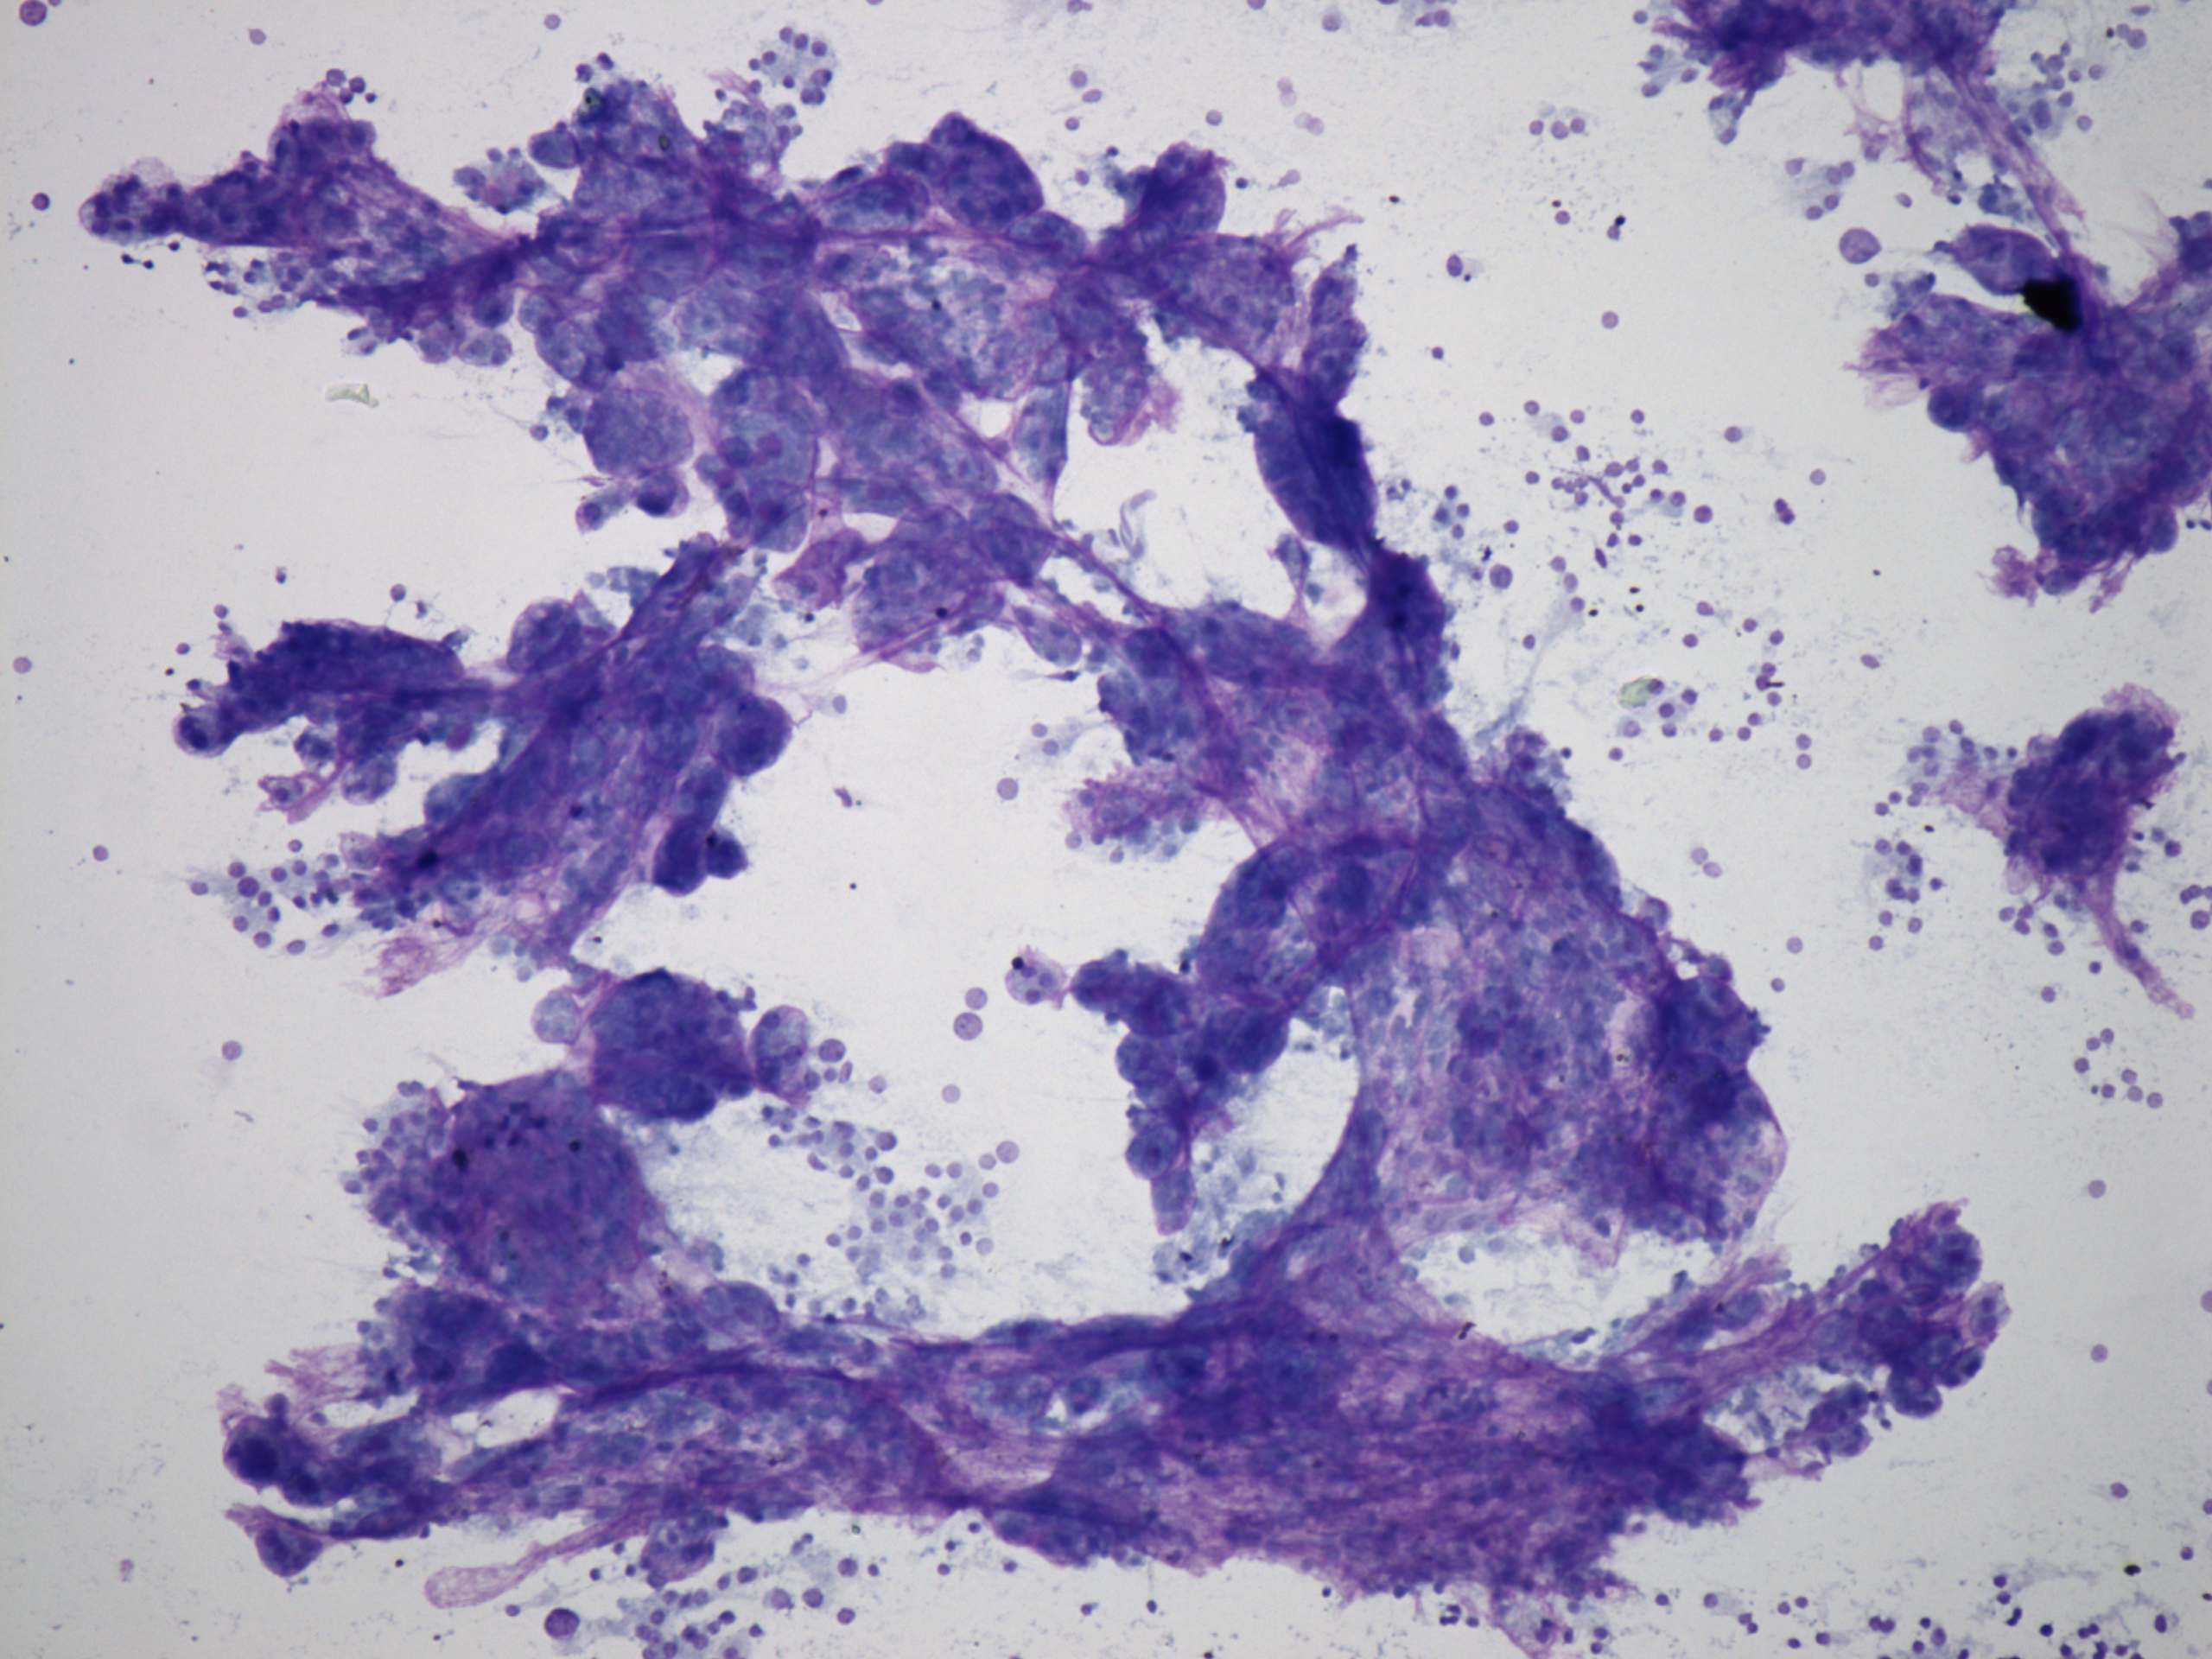

Benign nodular hyperplasia - Case 59. (cytologic picture 1)

Wright-Giemsa staining, 100x. There are large papillary clusters on the smear.